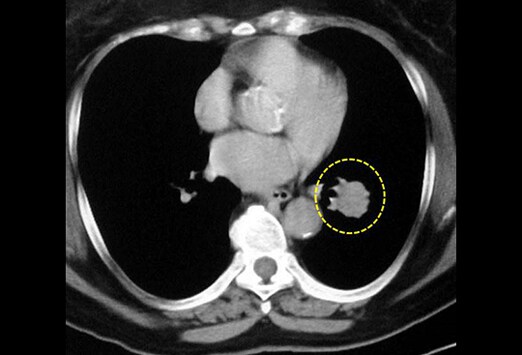

Chirurgie du cancer du poumon, orléans, région centre. Lsg lobe supérieur gauche. Lig lobe inférieur gauche. L. A. Chirurgie du cancer du poumon est classiquement réalisée par une thoracotomie (ouverture du thorax). Most cancers à petites cellules du poumon aspect au scanner. Cancer à petites cellules du poumon thing au scanner. Illustrations par de nombreuses coupes axiales et reconstructions coronales. Tumeur au foie, cancer, symptomes et traitement. Hyperplasie nodulaire focale. L’hyperplasie nodulaire focale est le deuxième most cancers du foie le plus fréquent. Elle est caractérisée par los angeles formation de nodules. Most cancers du poumon wikipédia. Phase d'un poumon humain. Los angeles partie blanche du lobe supérieur est cancéreuse ; les parties grises sont décolourées par le tabagisme spécialité oncologie. Cancer au poumon droit santémédecine. J'ai été opéré en juin 1998 d'un cancer au lobe supérieur gauche ( tumeur de 4cm sur 2cm) lobectomie + chimiothérapie 4mois. En decembre 2002, nodules au poumon.

Infocancer arcagy gineco localisations voies. Sa motive l. A. Plus fréquente est un cancer du poumon touchant le lobe supérieur du poumon par atteinte du nerf récontemporary gauche commandant les cordes. Syndrome de los angeles veine cave supérieure urgencesonline. Anatomophysiopathologie la veine cave supérieure draine le sang veineux de l. A. Tête et de la moitié supérieure du tronc et contribue au (). Most cancers du poumon wikipédia. Segment d'un poumon humain. La partie blanche du lobe supérieur est cancéreuse ; les events grises sont décolorationées par le tabagisme spécialité oncologie. Lobe moyen définition du mot lobe moyen doctissimo. Définition du mot lobe moyen les poumons droit et gauche présentent des scissures qui divisent l'ensemble en lobes plus petits. Le poumon gauche (sur l. A. Gauche du. Lymph drainage of the superior lobe of the left lung. Drainage lymphatique du lobe supérieur du poumon gauche (étude basée sur 50 injections). Tumeurs du poumon, primitives et secondaires. Parmi l’ensemble des tumeurs malignes, le cancer bronchopulmonaire est los angeles localisation cancéreuse qui a le plus progressé depuis la seconde guerre mondiale. Chirurgie du poumon youtube. · exemple au chu d'amiens avec le dr pascal berna sur une patiente ayant un most cancers du poumon. Lobe d'un poumon most cancers du poumon los angeles chirurgie.